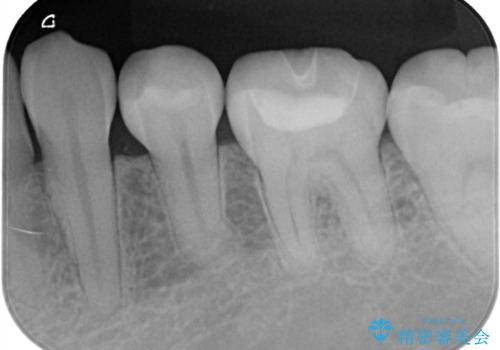

詰め物の下が黒いのが気になる セラミックインレー修復

- 定期健診の際に、他院の詰め物の下が黒くなっているのが気になるとのことで、セラミックインレーで治療し直したケースです。色調も調和しており、術後の経過も良好です。

セラミックは化学的に安定している為、長期的に見て素材自体の変質はありません。また摩耗にも強いため、臼歯部などの咬合力が強い部分にはレジンではなくセラミックを選ぶことをお勧めしています。